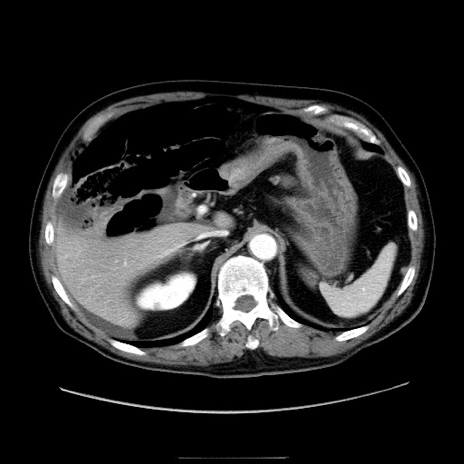

症例30(横断像)

【症例】80歳代男性

【主訴】臍周囲痛

【現病歴】約6時間前から臍下部痛が出現。次第に腹部膨隆・背部痛も生じてきたため来院。背部痛の場所は変化しない。

【身体所見】意識清明、BT 36.3℃、BP  131/87mmHg、P 87bpm、SpO2 100%(RA)、臍周囲自発痛・圧痛あり、反跳痛なし、自発痛部位に一致して板状硬あり、腹部膨隆、腸雑音減弱、CVA tenderness両側陰性。